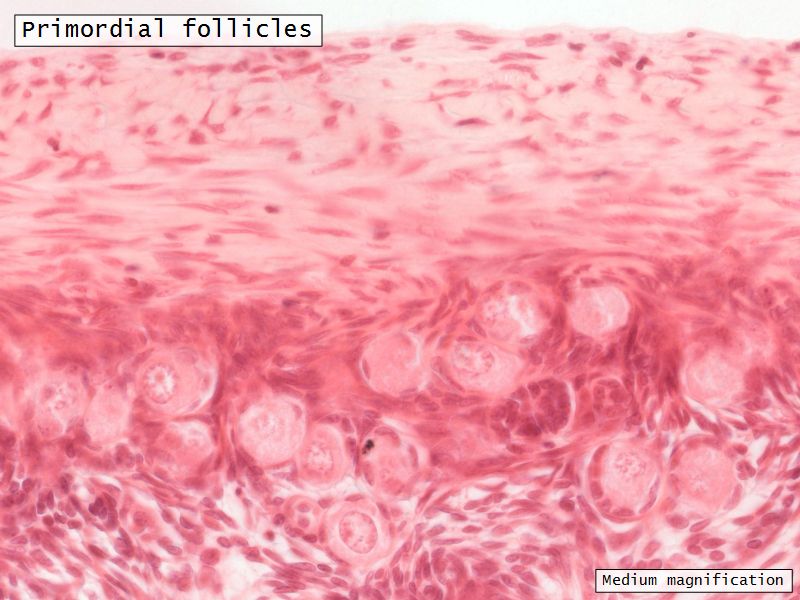

Follicular maturation

- Primordial follicle

- Growing follicle

- Primary follicle

- Secondary follicle

- Mature follicle (Graafian)

Components of a follicle

- Theca

- externa

- interna

- basal lamina

- Granulosa cells

- Antrum

- Cumulus oophorus >> Corona radiata

- Oocyte